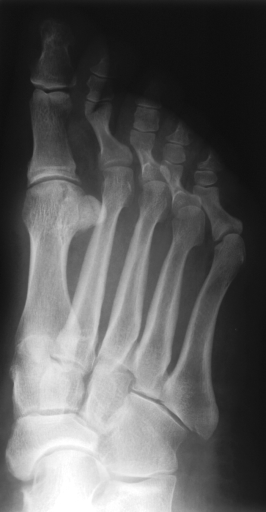

In this series of experiments, we randomly selected three categories from IRMA dataset (namely, breast, foot and lung), and for each category we choose 5 random images from that class (Figures 5, 6 and 7 show these images). When we find “4 out of 180” (4/180) and “8 out of 180” (8/180) projections via micro-DE (tasks that cannot be performed via brute-force), then the question is what can we say about the reconstruction error, in terms of correlation between original and reconstructed images, when we compare evolutionary approximation with the case that we can manage via exhaustive search, namely “4 out of 16” (4/16)? Can micro-DE reach at least the same correlation (similarity) as the brute-force case in lower dimensions? If yes, we may have more confidence in using micro-DE in practice where we cannot apply brute force for benchmarking or direct use, especially for higher dimensions (i.e., the number of projections).

For finding optimal projections based on micro-DE (4 out of 180), we set the parameters of micro-DE to be NFC, , , , and we run each experiment 30 times. For optimal projections based on micro-DE (8 out of 180), we set NFC, , , , and we run each experiment 30 times. The results are presented in Tables 2, 3 and 4. In all cases, micro-DE (MDE) with 4/180 reaches the same correlations as brute force (BF) for 4/16. Of course, MDE finds different projections as it is searching the entire search space of . However, that the same level of reconstruction accuracy can be achieved establishes the reliability of MDE as a practical solution that may even produce a higher-level of uniqueness for Radon barcodes as 4 projections are selected among all 180 angles (the increased uniqueness needs to be verified by applying the Radon barcodes for image retrieval). On the other hand, MDE for 8/180 clearly increases the correlation with statistical significance. This is very encouraging as we can generate more expressive Radon barcodes using a higher number of projections.

| image | BF (4/16) | MDE (4/180) | MDE (8/180) | |||

|---|---|---|---|---|---|---|

| f1 | [34,67,112,157] | 0.79 | [30,80,110,150] | 0.80 | [80,160,30,130,30,100,140,60] | 0.85 |

| f2 | [79,101,135,169] | 0.73 | [80,110,140,170] | 0.73 | [70,20,160,0,120,80,130,100] | 0.80 |

| f3 | [11,56,112,158] | 0.64 | [20,60,100,170] | 0.65 | [40,130,160,70,10,170,110,60] | 0.70 |

| f4 | [11,79,101,169] | 0.77 | [0,30,80,100] | 0.77 | [20,180,50,60,80,110,170,120] | 0.84 |

| f5 | [22,67,112,157] | 0.85 | [80,30,120,160] | 0.86 | [120,60,80,10,150,100,170,40] | 0.89 |